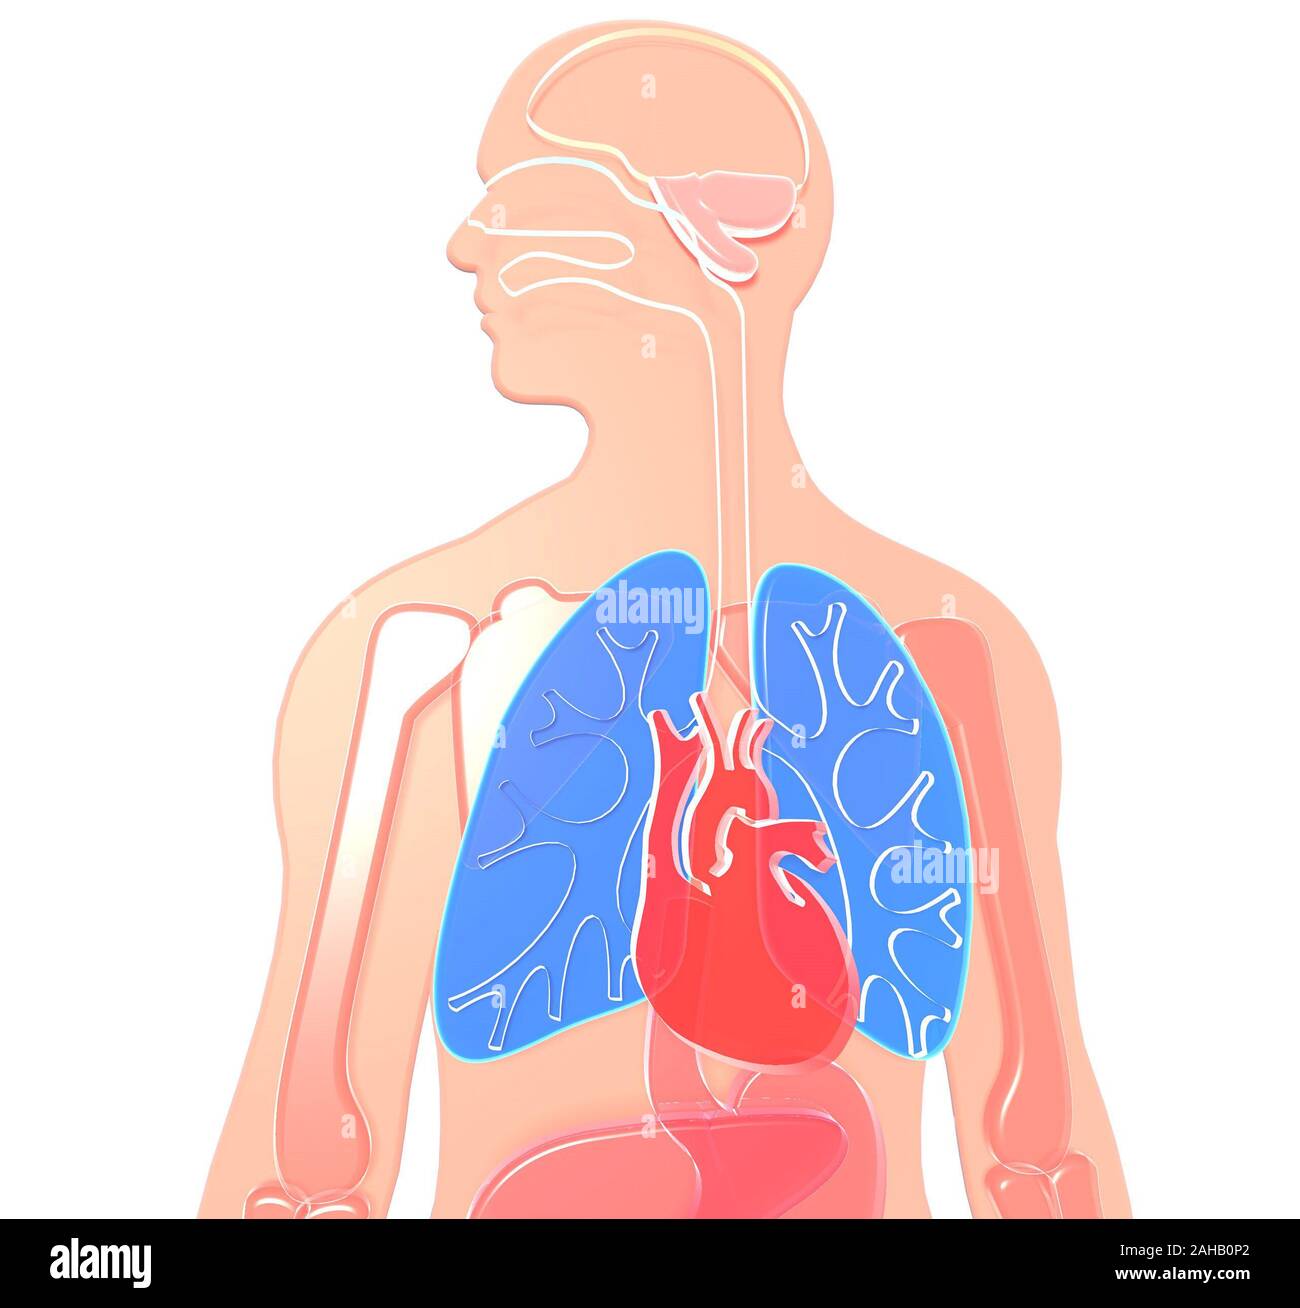

3D illustration human anatomy made of semitransparent plastic, lungs and heart highlighted, brain, kidneys, stomach, bones, liver. White background. Stock Photohttps://www.alamy.com/image-license-details/?v=1https://www.alamy.com/3d-illustration-human-anatomy-made-of-semitransparent-plastic-lungs-and-heart-highlighted-brain-kidneys-stomach-bones-liver-white-background-image337688234.html

3D illustration human anatomy made of semitransparent plastic, lungs and heart highlighted, brain, kidneys, stomach, bones, liver. White background. Stock Photohttps://www.alamy.com/image-license-details/?v=1https://www.alamy.com/3d-illustration-human-anatomy-made-of-semitransparent-plastic-lungs-and-heart-highlighted-brain-kidneys-stomach-bones-liver-white-background-image337688234.htmlRF2AHB0P2–3D illustration human anatomy made of semitransparent plastic, lungs and heart highlighted, brain, kidneys, stomach, bones, liver. White background.